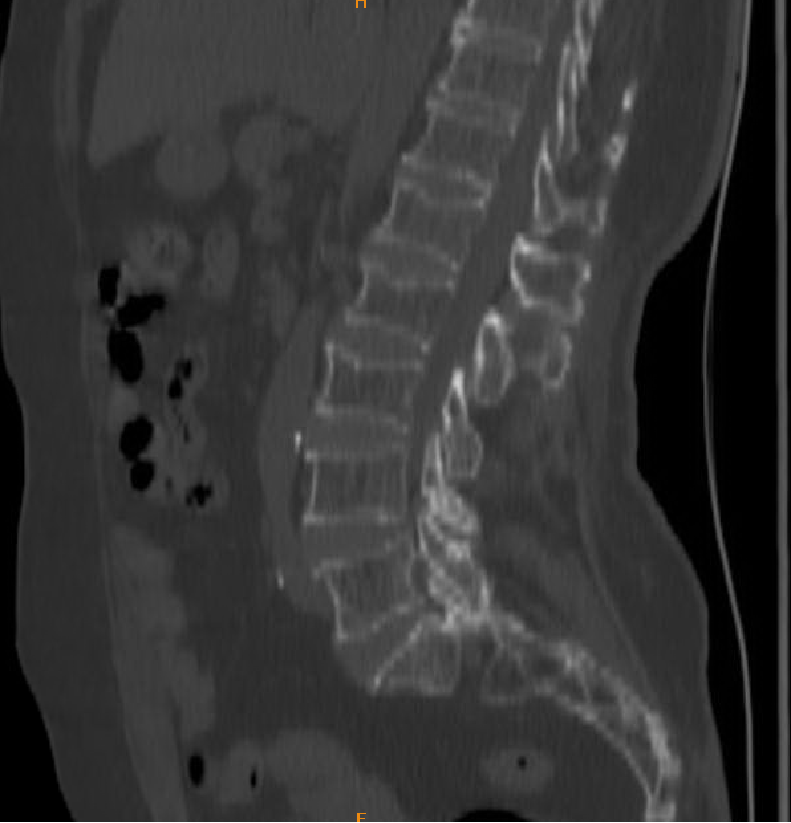

1、影像学检查

4、腰椎2、3压缩性骨折(陈旧性)